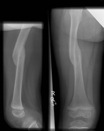

Subtrochanteric fractures

Issues

Non operative treatment rarely indicated in older children as acceptable alignment hard to maintain

- TENS technically more difficult

Options

Plate v TENS

Xu et al. Medicine 2018 PDF

- no difference in outcome between plate and TENS

- plate patients tended to be older and heavier